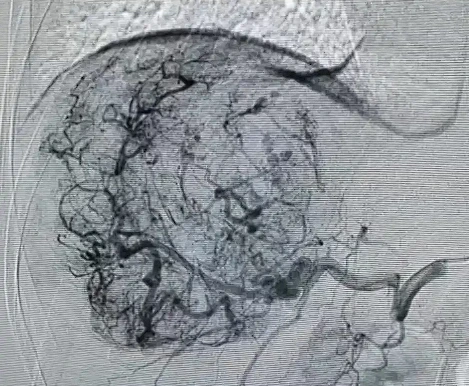

TACE是指使用抗癌药物经股动脉选择性肝动脉插管化疗栓塞术,将导管插入到为肿瘤供血的动脉后,以适当的速度注入栓塞剂,使该动脉闭塞,引起肿瘤组织的缺血坏死。

HAIC是经股动脉插管至肝肿瘤供血动脉内并保留导管,将化疗药持续注入肿瘤供血动脉的一种区域性局部化疗,对弥漫型或合并门静脉瘤栓的肝癌患者有明显优势。